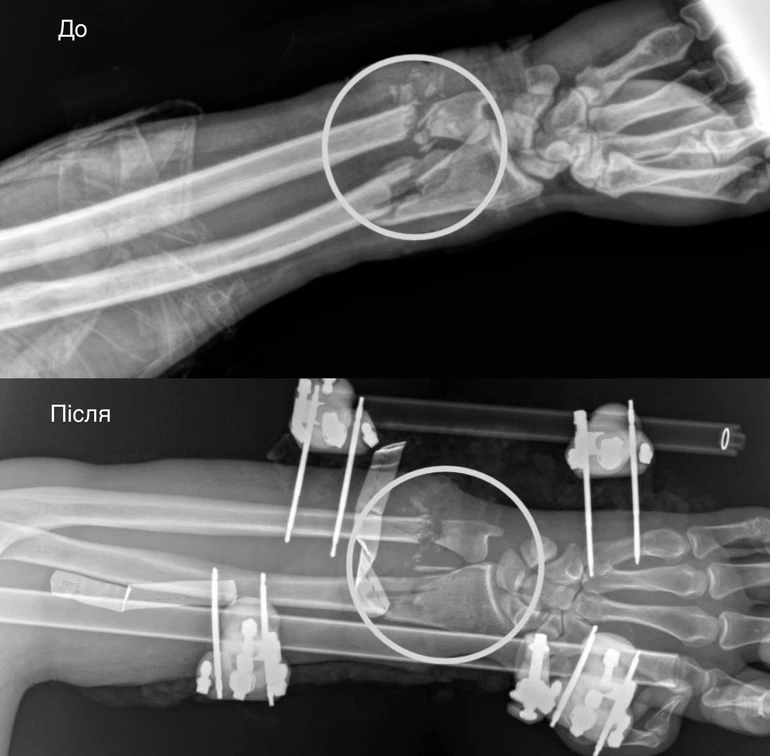

Травма була критичною: рука фактично трималася лише на шкірі. В чоловіка були повністю пересічені артерії, пошкоджені кістки, м’язи, сухожилля та нерви. За порятунок кінцівки взялася мультидисциплінарна команда медиків.

Спершу ортопеди-травматологи стабілізували переломи за допомогою апарата зовнішньої фіксації. Далі судинні хірурги відновили кровопостачання, зшивши пошкоджені судини – саме цей етап був вирішальним, адже без циркуляції крові тканини швидко змертвіли б.